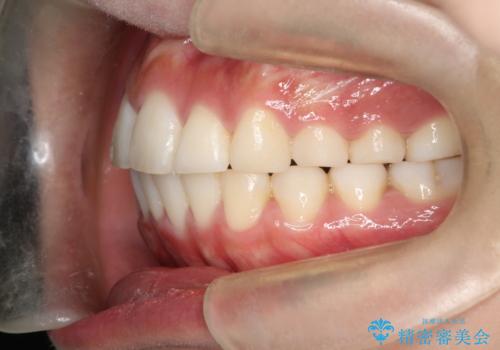

上下の前歯の距離が近くなり、前歯で咬みやすくなり、審美的にも改善できました。